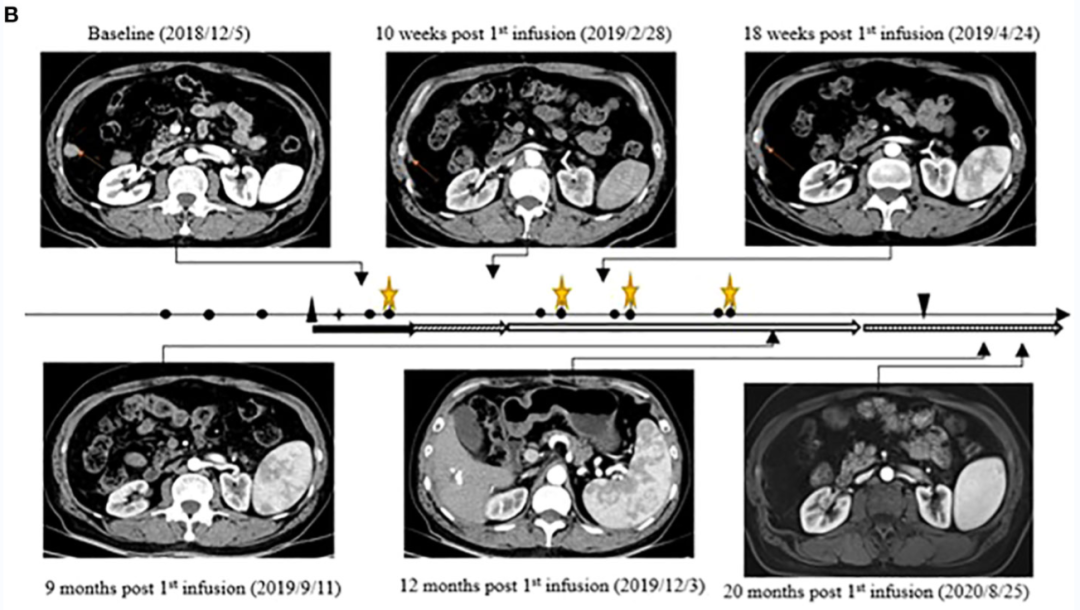

晚期肝癌的M先生万万没有想到,4年前的手术和介入治疗并没有阻止病情快速进展,癌细胞已经扩散到肺部...后来竟然幸运的在中国接受了全球最前沿的免疫疗法之一--CAR-T,联合索拉菲尼治疗后,他的病灶全部消失,并且完全缓解长达2年多,他的成功案例也被刊登在国际知名免疫学期刊《Frontiers in Immunology》杂志上,值得一提的是,这是CAR-T细胞与靶向药联合治疗后报告的首个完全缓解病例,具有里程碑式的意义,也给无数肝癌患者点亮了新的希望!

医生用M先生体内免疫细胞,通过前沿的基因工程技术,专门制备出针对GPC3阳性癌细胞的“特种兵”--GPC3 CAR-T,并扩增出庞大的数量,当40亿(4×109) 个GPC3 CAR-T细胞回输到M先生体内后,甲胎蛋白从6047 ng/ml持续下降至正常值(≤9 ng/mL),之后一直保持正常!

在第一个回输周期后的第12个月达到完全缓解,这意味着朴大爷体内的靶病灶已经完全消失了。

更值得一提的是,肿瘤超过36个月没有进展,在第一次输注后保持完全缓解状态超过24个月!